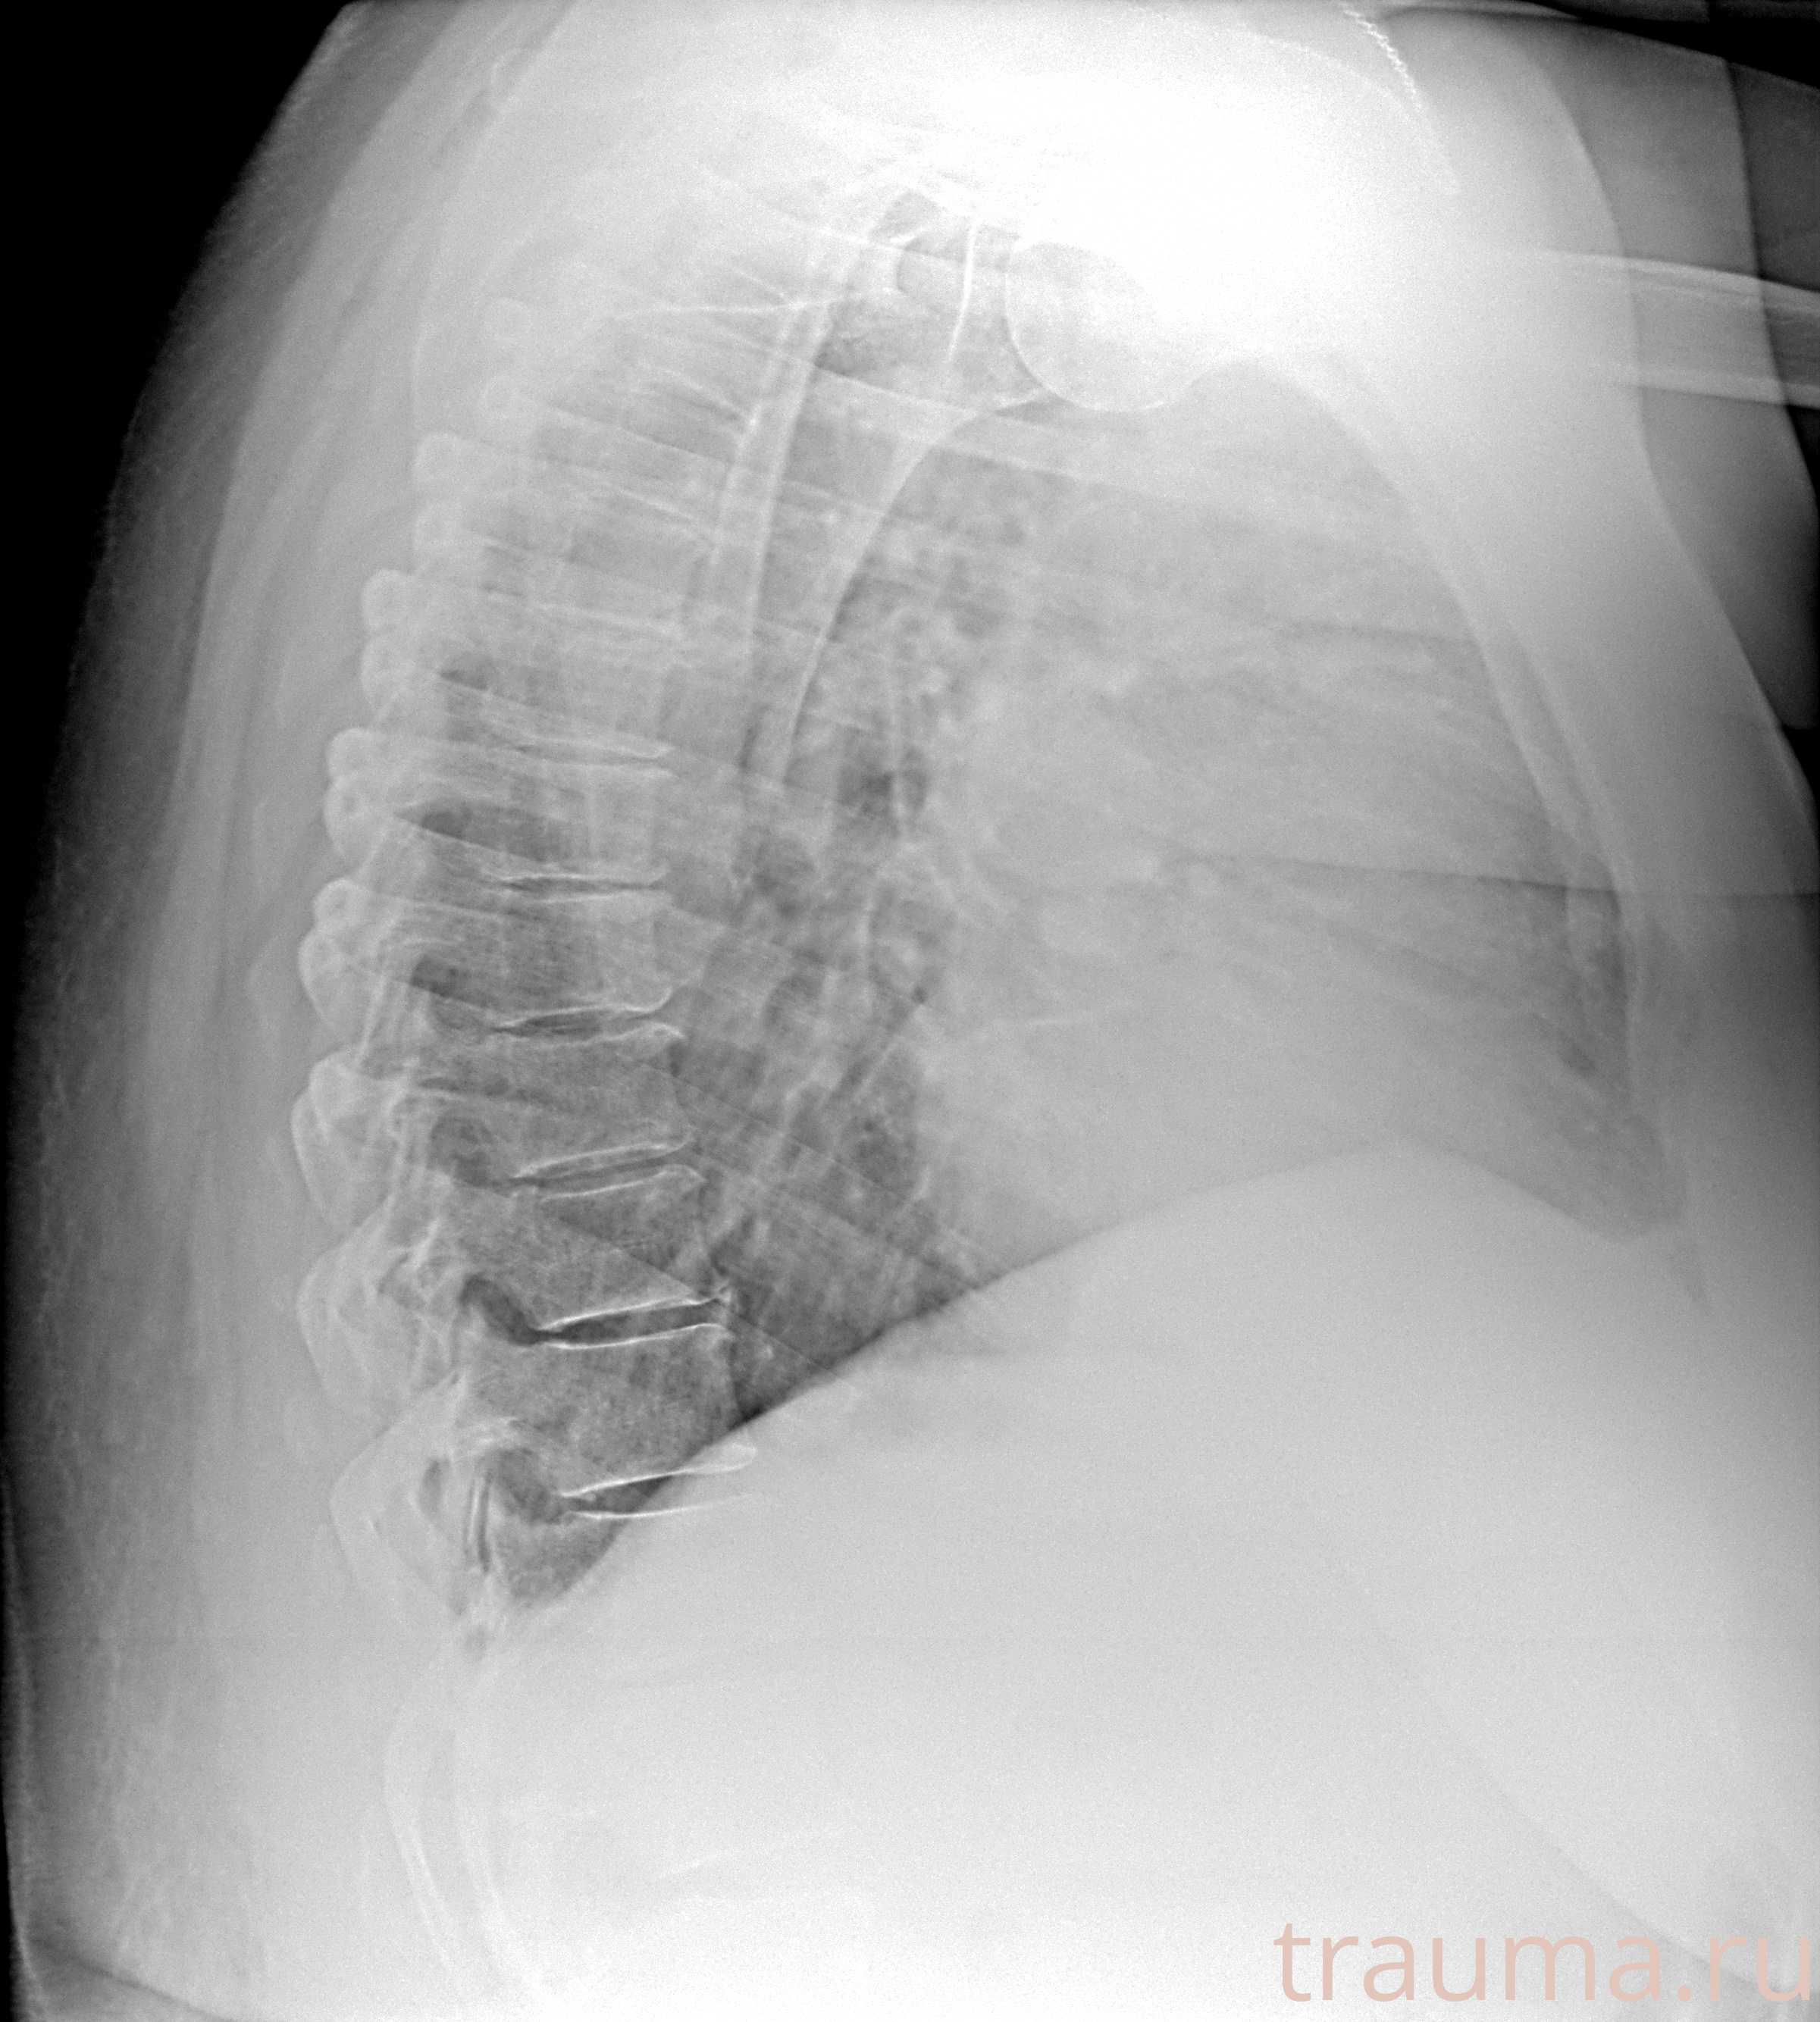

Рентгенограммы

Рентген на дому: по вашему адресу приезжает врач-рентгенолог, травматолог-ортопед с мобильным рентгеновским аппаратом, проводит диагностику травмы или заболевания, делает необходимые рентгенограммы, дает рекомендации по дальнейшему лечению. Получить качественные снимки в домашних условиях возможно благодаря уникальной методике, разработанной МосРентген Центром для института  Склифосовского